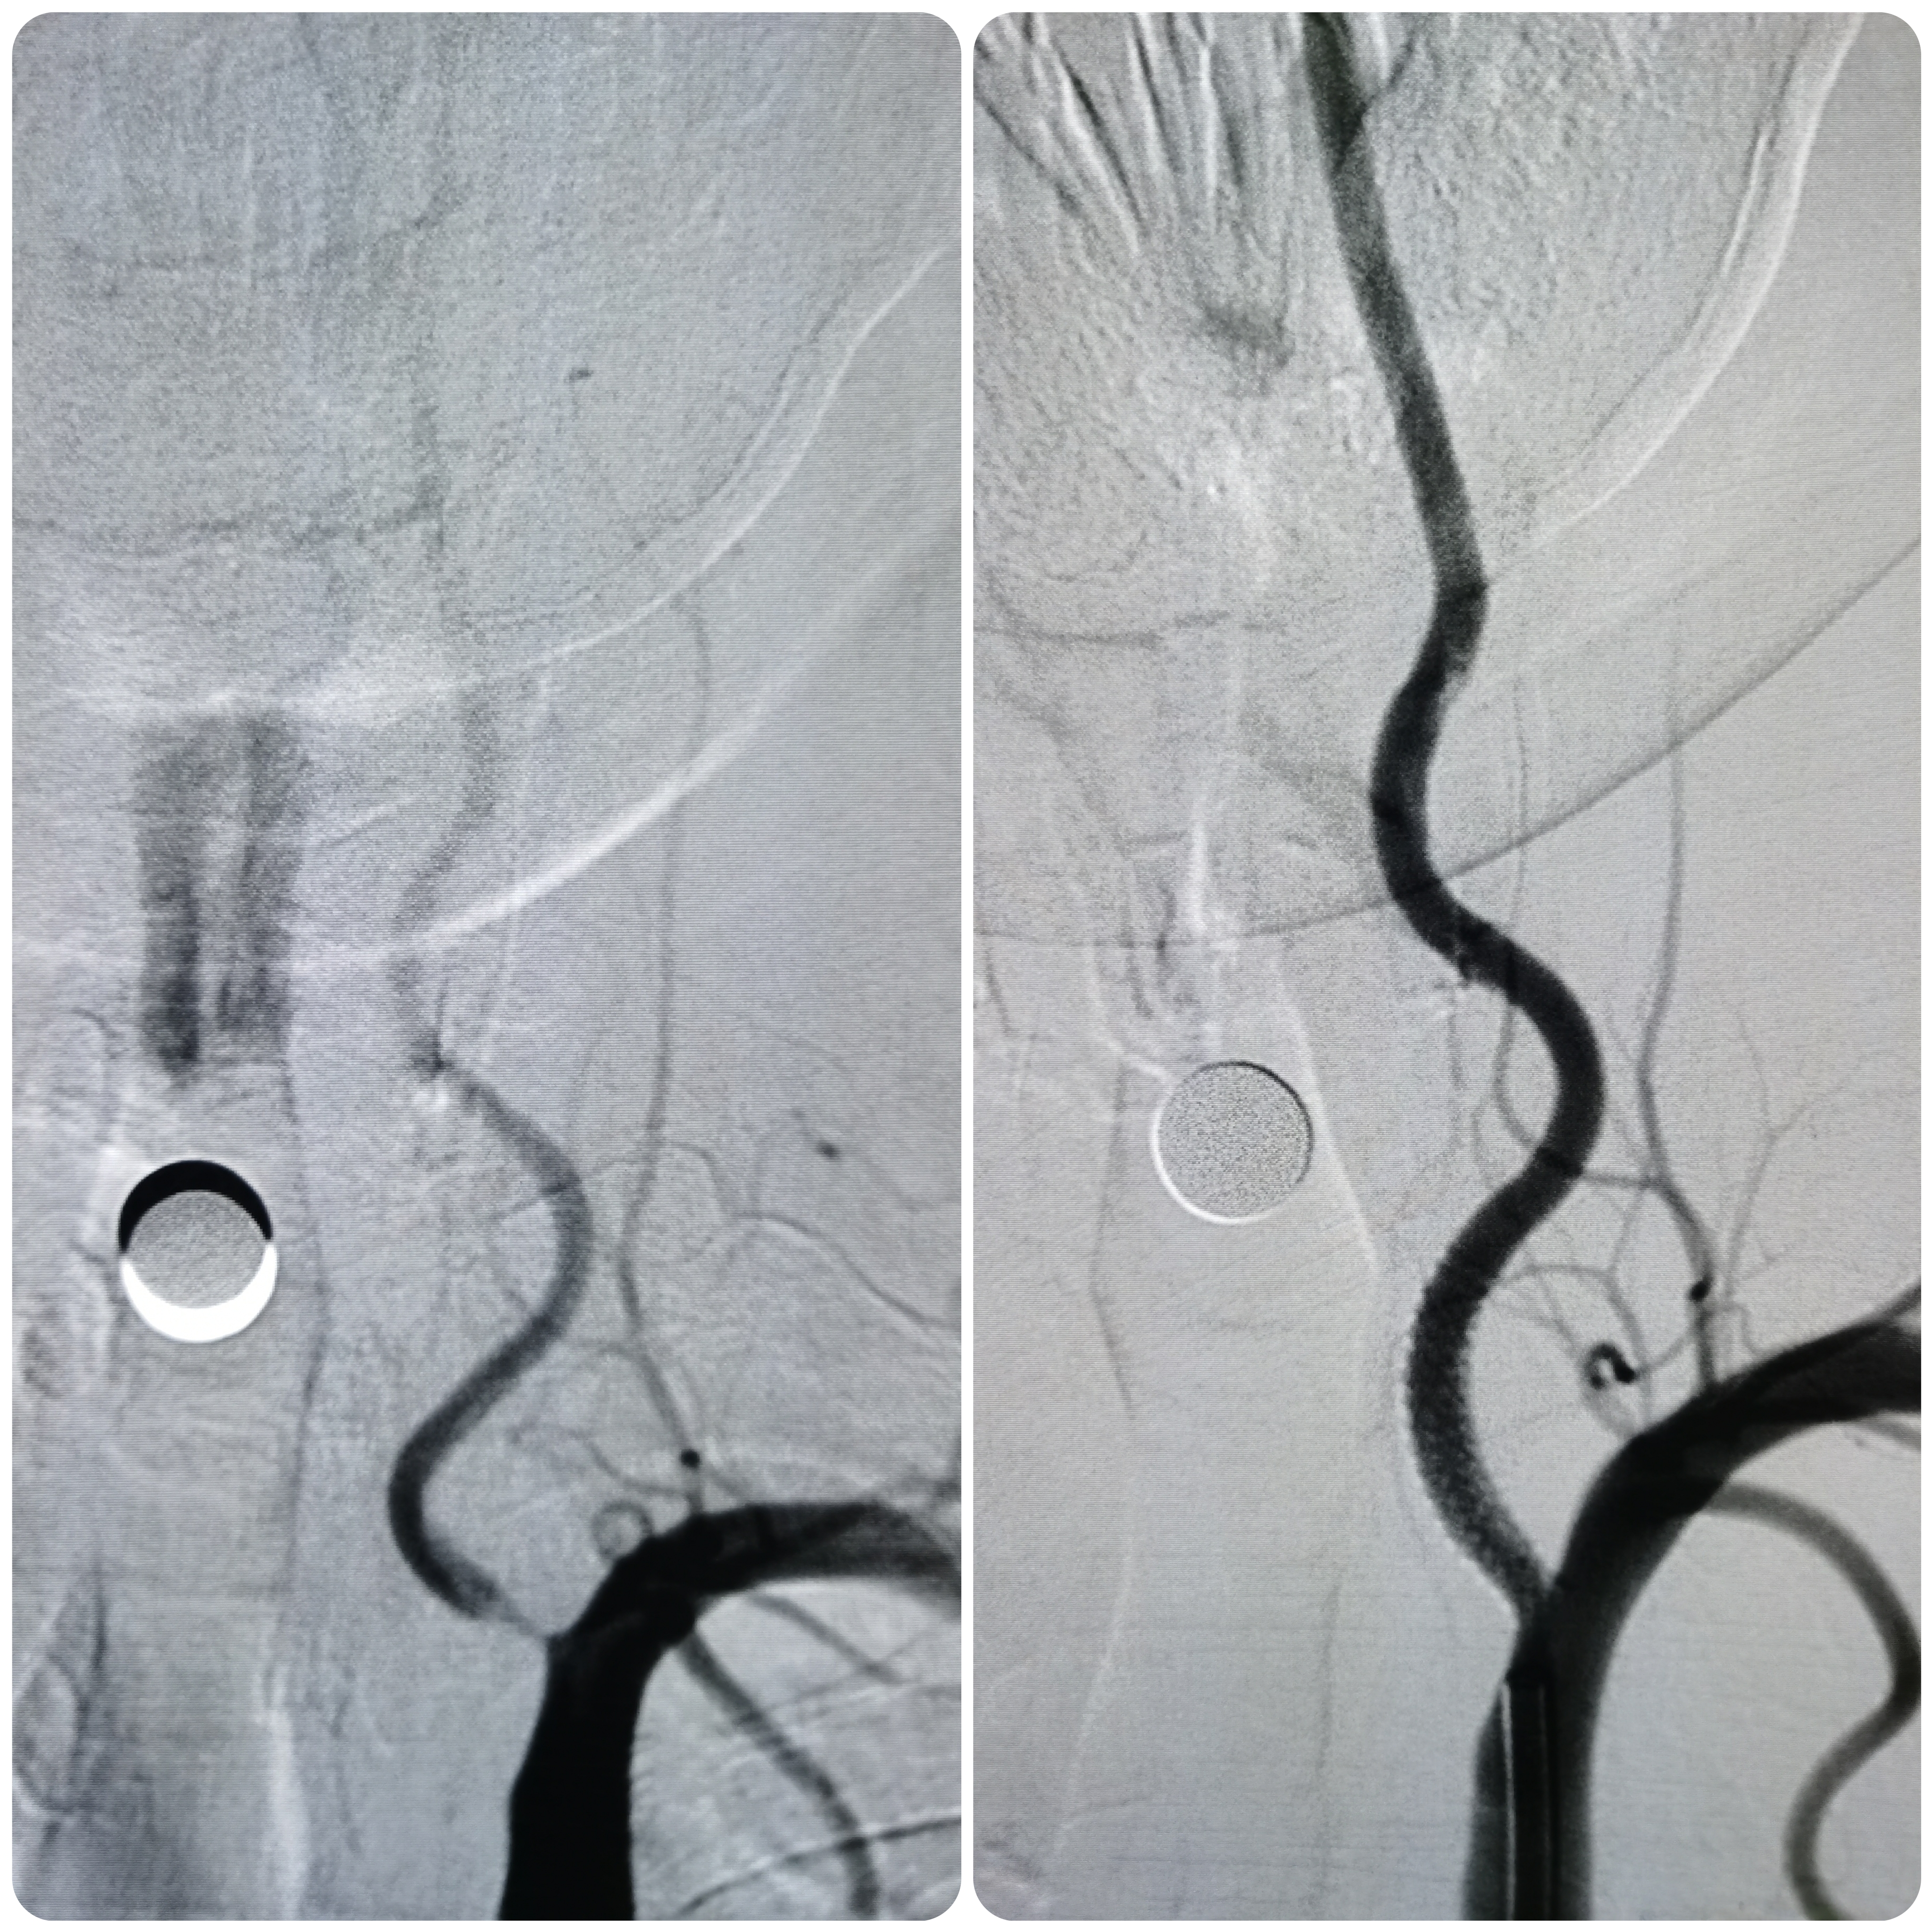

将8F导引导管送至左侧锁骨下动脉近左椎动脉起始部,微导丝顺利通过病变,2.0/20球囊预扩病变。

2、CTA证实左椎动脉起始部重度狭窄合并血栓,系责任血管,存在急性闭塞或残存血栓脱落至基底动脉风险,需积极处理。

3、手术过程中,先用小球囊扩张病变,观察血栓情况,及时应用支架全程覆盖血栓及病变部位,成形满意。